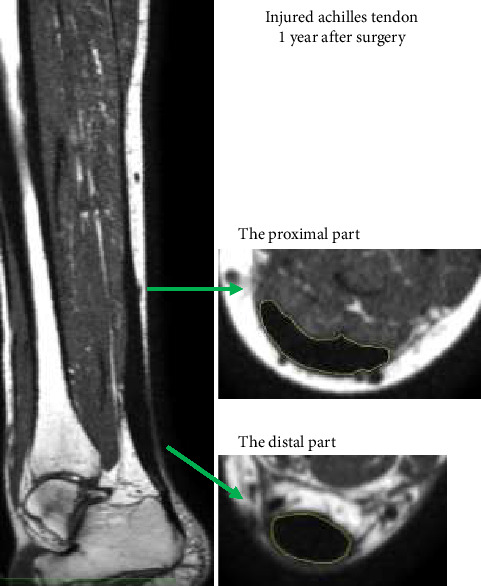

Purpose: This study investigated effects of delayed initial loading in comparison to a standard regime following an Achilles tendon rupture (ATR) on tendon cross-sectional area (CSA) and fat infiltration by using 3D magnetic resonance imaging (MRI) and ultrasound (US) measurements. Methods: Secondary analysis of a randomized controlled trial. Forty-eight patients with an ATR were randomized to a Standard regime with weight-bearing after 6 weeks or a Delayed regime with weight-bearing after 12 weeks postsurgery. Achilles tendon CSA, fat fraction, and vascularization were measured on both the injured and the uninjured side using MRI and US at 12 and 52 weeks. Results: The injured tendon was significantly larger (> 300%) than the uninjured tendon for both the distal and proximal parts (p < 0.0001). The CSA of the distal part was smaller in the Delayed group at 3 months (p=0.038), but not at 12 months. Fat fraction in the tendon increased in both groups. The Delayed group had significantly less vascularization compared with the Standard group at 3 months, and the vascularization decreased in both groups from 3 to 12 months. Conclusion: In comparison to the Standard treatment, the Delayed group had reduced CSA and vascularization for the distal part of the tendon after 3 months. After a year, these differences had become insignificant. From 3 to 12 months, the distal parts of the injured tendon showed an accumulation of fat in both groups. Not only the rupture site but also the entire tendon was affected by the inflammatory repair response. Trial Registration: ClinicalTrials.gov identifier: NCT04263493.